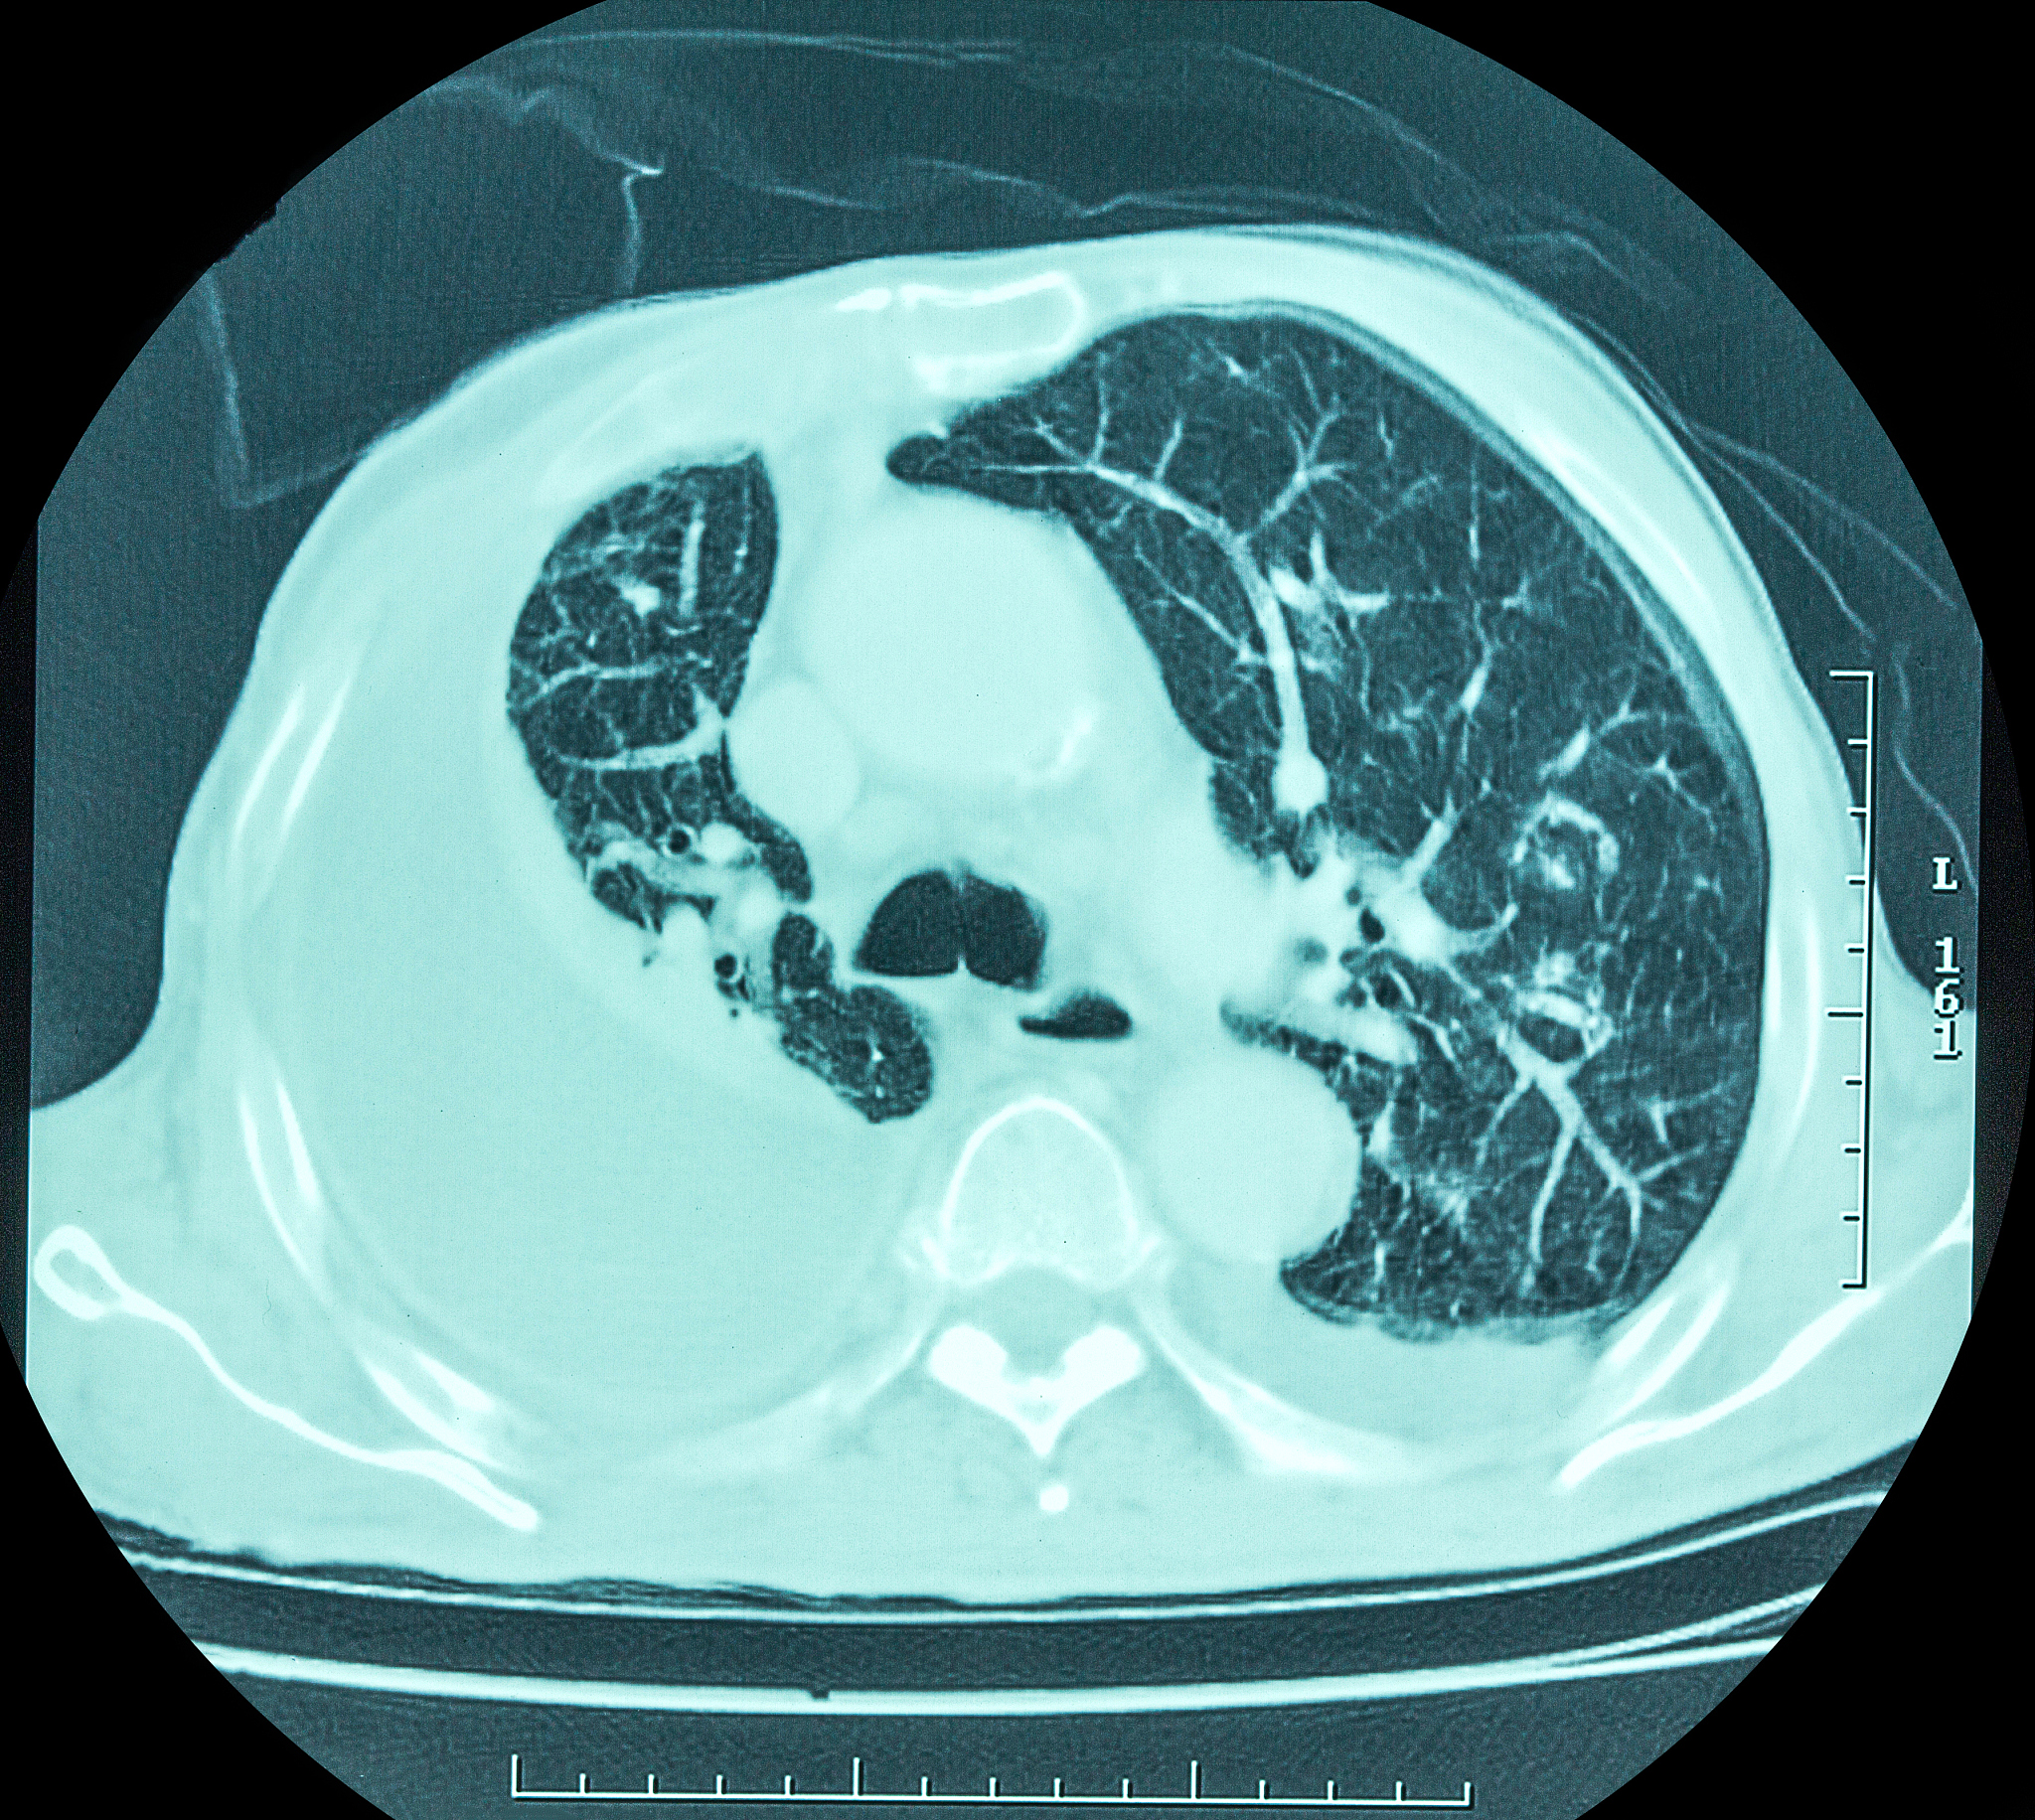

闭合性胸腹部损伤合并创伤性脾破裂:腹腔镜探查与开腹术中麻醉配合及体征监护

闭合性胸腹部损伤合并创伤性脾破裂属于外科急症,常需紧急手术治疗。腹腔镜探查和开腹探查是两种常用的手术方式。无论选择哪种方式,术中麻醉配合和体征监护都至关重要,直接关系到手术的安全和成功。